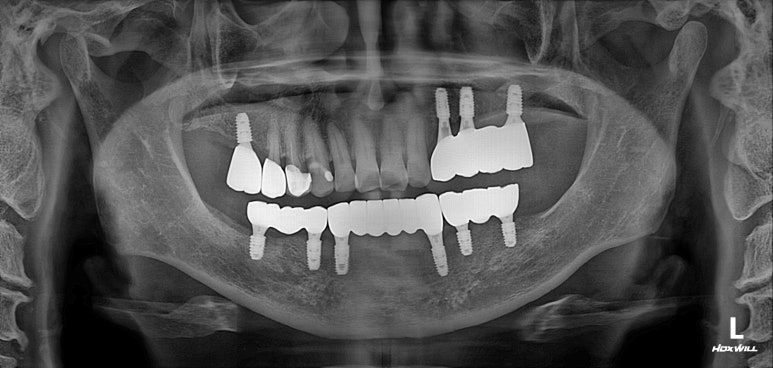

치료가 마무리된 후의 치과용 파노라마 사진입니다.

정~~~말 깔끔하게 마무리가 잘 되었네요!!!

확인하실 수 있듯, 아래턱의 경우 단 6개의 임플란트만 심었음에도 불구하고, 총 12개의 치아를 만들어드릴 수 있었습니다. 위턱의 경우 좌측 3개, 우측 1개의 임플란트로 총 5개의 치아를 만들어드린 상태입니다.

치과용 파노라마를 촬영하여 뼈 속의 임플란트 고정체와 제작한 맞춤형 지대주 (custom abutment)가 잘 연결되어있는지 확인할 수 있었습니다. 아직 임시치아이기에 엑스레이에서는 마치 없는 것처럼 흐릿하게 보이네요.

이렇게까지 제작해드리는데, 위턱에는 4개의 임플란트 아래턱에는 6개의 임플란트만 사용하였을 뿐입니다.